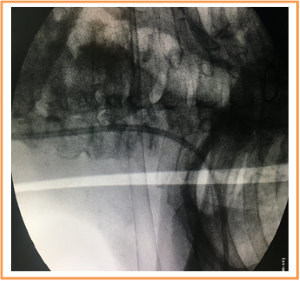

This procedure was done without fluoroscopic screening in the first 20 patients (21.5%) then used under fluoroscopic screening in the last 73 patients (78.5%) (Figure 4).

Mal-position was occurred in 4 patients who underwent implantation without screening and managed by catheter redirection under screening guidance. (Figure 7), Pulmonary embolism was never found. Wound bleeding was developed in 3 patients that required re-admission to the theater and stopping the bleeding. One patient developed hematoma that resolved conservatively. The accidental arterial puncture occurred in 6 patients for whom PAC was inserted without US guidance and managed simply by direct pressure without surgical intervention.